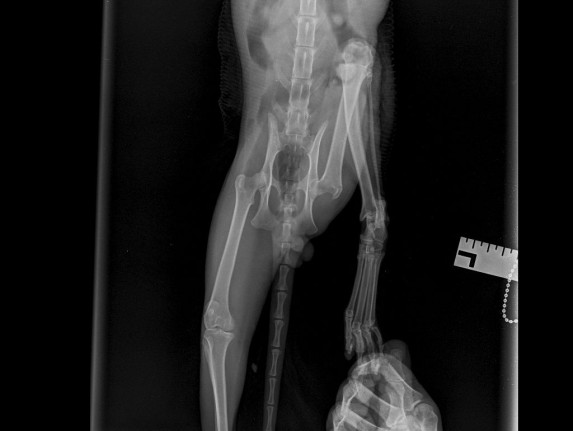

| История болезней/травм | 28.12.2025 - скальп кожи с бедра левой лапы и укол в колено. Где-то зацепился и потянул. Месяц так проходил, никто не помогал. Благодаря морозу заражения сильного не было. Обращение в ветклинику "КОТоПЁС": осмотр, стрижка, чистка раны солевым раствором, наложение повязки с лекарством (септо-спрей, бранолинд) и антибиотики (Кладакса, Марфлоксин) с обезболивающим, рентген. 29.12.2025 - Обращение в ветклинику "КОТоПЁС": осмотр, чистка раны солевым раствором, наложение повязки с лекарством (септо-спрей, бранолинд) и антибиотики с обезболивающим. 30.12.2026 - антибиотики. 31.12.2025 - Обращение в ветклинику "Эмили": чистка раны солевым раствором, наложение повязки с лекарством (септо-спрей, бранолинд) и антибиотики. 01.01.2026 - антибиотики. 02.01.2026 - чистка раны солевым раствором, наложение повязки с лекарством (септо-спрей, бранолинд) и антибиотики. 03.01.2026 - антибиотики. 04.01.2026 - Обращение в ветклинику "КОТоПЁС": осмотр, чистка раны солевым раствором, наложение повязки с лекарством (септо-спрей, бранолинд) и антибиотики, рентген. 05.01.2026 - антибиотики. 06.01.2026 - чистка раны солевым раствором, наложение повязки с лекарством (септо-спрей, бранолинд) и антибиотики. 07.01.2026 - антибиотики. 08.01.2026 - чистка раны солевым раствором, наложение повязки с лекарством (септо-спрей, бранолинд) и антибиотики. 10.01.2026 - Обращение в ветклинику "КОТоПЁС": осмотр, чистка раны солевым раствором, наложение повязки с лекарством (септо-спрей, бранолинд) и антибиотики. 11.01.2026 - антибиотики, глистогонка. 12.01.2026 - чистка раны солевым раствором, наложение повязки с лекарством (септо-спрей, бранолинд) и антибиотики. 13.01.2026 - чистка раны солевым раствором, наложение повязки с лекарством (септо-спрей, бранолинд) и антибиотики. 14.01.2026 - антибиотики. 15.01.2026 - антибиотики. 16.01.2026 - чистка раны солевым раствором, наложение повязки с лекарством (септо-спрей, бранолинд) и антибиотики. 17.01.2026 - антибиотики. 18.01.2026 - антибиотики. 19.01.2026 - чистка раны солевым раствором, наложение повязки с лекарством (септо-спрей, бранолинд) и антибиотики. 20.01.2026 - чистка раны солевым раствором, наложение повязки с лекарством (септо-спрей, Повязка мазевая Исполнение-Д4 50х70) и антибиотики. 23.01.2026 - чистка раны солевым раствором, наложение повязки с лекарством (септо-спрей, Повязка мазевая Исполнение-Д4 50х70). 26.01.2026 - чистка раны солевым раствором, наложение повязки с лекарством (септо-спрей, Повязка мазевая Исполнение-Д4 50х70). 29.01.2026 - чистка раны солевым раствором, наложение повязки с лекарством (септо-спрей, Повязка мазевая Исполнение-Д4 50х70) и антибиотики. 30.01.2026 - антибиотики. 31.01.2026 - чистка раны солевым раствором, наложение повязки с лекарством (септо-спрей, бранолинд) и антибиотики. 01.02.2026 - антибиотики. 02.02.2026 - чистка раны солевым раствором, наложение повязки с лекарством (септо-спрей, бранолинд) и антибиотики. 03.02.2026 - чистка раны солевым раствором, наложение повязки с лекарством (септо-спрей, бранолинд). 04.02.2026 - чистка раны солевым раствором, наложение повязки с лекарством (септо-спрей, бранолинд). 06.02.2026 - чистка раны солевым раствором, наложение повязки с лекарством (септо-спрей, ихтиоловая мазь). 07.02.2026 - чистка раны солевым раствором, наложение повязки с лекарством (септо-спрей, бранолинд). 09.02.2026 - чистка раны солевым раствором, наложение повязки с лекарством (септо-спрей, бранолинд). 11.02.2026 - чистка раны солевым раствором, наложение повязки с лекарством (септо-спрей, бранолинд). 12.02.2026 - чистка раны солевым раствором, наложение повязки с лекарством (септо-спрей, бранолинд). 14.02.2026 - чистка раны солевым раствором, наложение повязки с лекарством (септо-спрей, бранолинд). 15.02.2026 - чистка раны солевым раствором, наложение повязки с лекарством (септо-спрей, Повязка мазевая Исполнение-Д4 50х70). 17.02.2026 - чистка раны солевым раствором, наложение повязки с лекарством (септо-спрей, Повязка мазевая Исполнение-Д4 50х70). 19.02.2026 - чистка раны солевым раствором, наложение повязки с лекарством (септо-спрей, Повязка мазевая Исполнение-Д4 50х70). 20.02.2026 - чистка раны солевым раствором, наложение повязки с лекарством (септо-спрей, ихтиоловая мазь). 22.02.2026 - чистка раны солевым раствором, наложение повязки с лекарством (септо-спрей, ихтиоловая мазь). 24.02.2026 - чистка раны солевым раствором, наложение повязки с лекарством (септо-спрей, ихтиоловая мазь). 26.02.2026 - чистка раны солевым раствором, наложение повязки с лекарством (септо-спрей, ихтиоловая мазь). 28.02.2026 - чистка раны солевым раствором, наложение повязки с лекарством (септо-спрей, ихтиоловая мазь). 02.03.2026 - чистка раны солевым раствором, наложение повязки с лекарством (септо-спрей, ихтиоловая мазь). 03.03.2026 - чистка раны солевым раствором, наложение повязки с лекарством (септо-спрей, ихтиоловая мазь). 04.03.2026 - чистка раны солевым раствором, наложение повязки с лекарством (септо-спрей, ихтиоловая мазь). 06.03.2026 - чистка раны солевым раствором, наложение повязки с лекарством (септо-спрей, ихтиоловая мазь). 07.03.2026 - чистка раны солевым раствором, наложение повязки с лекарством (септо-спрей, ихтиоловая мазь). 08.03.2026 - чистка раны солевым раствором, наложение повязки с лекарством (септо-спрей, ихтиоловая мазь). 10.03.2026 - чистка раны солевым раствором, наложение повязки с лекарством (септо-спрей, ихтиоловая мазь). 12.03.2026 - чистка раны солевым раствором, наложение повязки с лекарством (септо-спрей, ихтиоловая мазь). 14.03.2026 - чистка раны солевым раствором, наложение повязки с лекарством (йод и солевой раствор, ихтиоловая мазь). 16.03.2026 - чистка раны солевым раствором, наложение повязки с лекарством (йод и солевой раствор, ихтиоловая мазь) и антибиотики. 17.03.2026 - антибиотики. 18.03.2026 - чистка раны солевым раствором, наложение повязки с лекарством (йод и солевой раствор, ихтиоловая мазь) и антибиотики. 19.03.2026 - глистогонка "Дирофен". 20.03.2026 - чистка раны солевым раствором, наложение повязки с лекарством (йод и солевой раствор, ихтиоловая мазь) и антибиотики. 22.03.2026 - чистка раны солевым раствором, наложение повязки с лекарством (йод и солевой раствор, ихтиоловая мазь). 24.03.2026 - чистка раны солевым раствором, наложение повязки с лекарством (йод и солевой раствор, ихтиоловая мазь). 26.03.2026 - чистка раны солевым раствором, наложение повязки с лекарством (йод и солевой раствор, Повязка мазевая Исполнение-Д4 50х70) и антибиотики. 27.03.2026 - антибиотики. 28.03.2026 - чистка раны солевым раствором, наложение повязки с лекарством (йод и солевой раствор, Повязка мазевая Исполнение-Д4 50х70) и антибиотики. 29.03.2026 - антибиотик 30.03.2026 - чистка раны солевым раствором, наложение повязки с лекарством (йод и солевой раствор, Повязка мазевая Исполнение-Д4 50х70) и антибиотики. 31.03.2026 - антибиотик 01.04.2026 - чистка раны солевым раствором, наложение повязки с лекарством (йод и солевой раствор, Повязка мазевая Исполнение-Д4 50х70). 04.04.2026 - чистка раны солевым раствором, наложение повязки с лекарством (йод и солевой раствор, ихтиоловая мазь). 06.04.2026 - чистка раны солевым раствором, наложение повязки с лекарством (йод и солевой раствор, Повязка мазевая Исполнение-Д4 50х70). 08.04.2026 - чистка раны солевым раствором, наложение повязки с лекарством (йод и солевой раствор, Повязка мазевая Исполнение-Д4 50х70). 10.04.2026 - чистка раны солевым раствором, наложение повязки с лекарством (йод и солевой раствор, Повязка мазевая Исполнение-Д4 50х70). 12.04.2026 - чистка раны солевым раствором, наложение повязки с лекарством (йод и солевой раствор, Повязка мазевая Исполнение-Д4 50х70). 14.04.2026 - чистка раны солевым раствором, наложение повязки с лекарством (йод и солевой раствор, Повязка мазевая Исполнение-Д4 50х70), глистогонка "Дирофен" и антибиотик (Кладакса). Заметно перестаёт кушать. 15.04.2026 - антибиотик (Кладакса). Плохо ест сам. 16.04.2026 - чистка раны солевым раствором, наложение повязки с лекарством (йод и солевой раствор, Повязка мазевая Исполнение-Д4 50х70) и антибиотик (Кладакса). 17.04.2026 - антибиотик (Кладакса). Ест только рыбку. 18.04.2026 - чистка раны солевым раствором, наложение повязки с лекарством (йод и солевой раствор, Повязка мазевая Исполнение-Д4 50х70) и антибиотик (Кладакса). 20.04.2026 - чистка раны солевым раствором, наложение повязки с лекарством (йод и солевой раствор, Повязка мазевая Исполнение-Д4 50х70). Принудительное кормление паштетом, пьёт сам. 22.04.2026 - чистка раны солевым раствором, наложение повязки с лекарством (йод и солевой раствор, Повязка мазевая Исполнение-Д4 50х70). Принудительное кормление паштетом, пьёт сам. 24.04.2026 - чистка раны солевым раствором, наложение повязки с лекарством (йод и солевой раствор, Повязка мазевая Исполнение-Д4 50х70). Принудительное кормление паштетом, пьёт сам. 26.04.2026 - чистка раны солевым раствором, наложение повязки с лекарством (мазь стрептоцид и солевой раствор, Повязка мазевая Исполнение-Д4 50х70). Принудительное кормление паштетом и водой. 28.04.2026 - чистка раны солевым раствором, наложение повязки с лекарством (мазь стрептоцид и солевой раствор, Повязка мазевая Исполнение-Д4 50х70). Принудительное кормление паштетом и водой. 30.04.2026 - чистка раны солевым раствором, наложение повязки с лекарством (йод и солевой раствор, ихтиоловая мазь). Принудительное кормление паштетом и водой. Обращение в ветклинику "ЭМИЛИ". 01.05.2026 - Обращение в ветклинику "ЭМИЛИ" - диагноз ФИП, откачка 300 мл жидкости из брюшной полости. Капельница и приём Коронакэт. 02.05.2026 - смерть. |